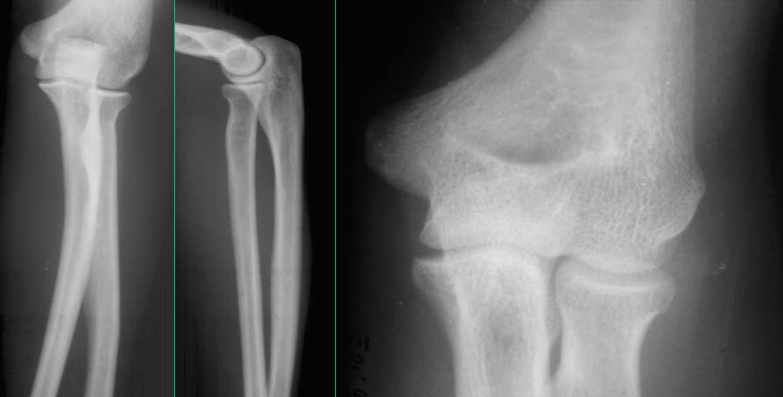

肘关节 由肱骨下端和桡、尺骨的上端构成的复关节

(1)构成: 1.肱尺关节:由肱骨滑车和尺骨滑车切迹构成。

2肱桡关节:由肱骨小头和桡骨头的关节凹构成。

3.桡尺近侧关节:由桡骨环状关节面和尺骨桡切迹构成。

特点:1.三个关节包在一个关节囊内; 2.囊的前、后壁薄而松弛,后壁最薄弱,桡、尺骨易向后脱位,两侧壁厚而紧张,并有桡侧副韧带、尺侧副韧带和桡骨环状韧带加强。

运动:肘关节可作屈、伸运动。伸肘时,前臂偏向外侧与臂部形成约163°的提携角。屈肘时,桡骨内上、外上和鹰嘴之间形成一个等腰三角形,肘关节脱位时,这种正常比例关系发生改变。

肘关节脱位:

此三角关系—判断肘关节脱位和肱骨髁上骨折标志

- 病因:最常见的脱位之一(仅次于肩关节),多发生于青壮年,关节后脱位多见,肘关节后脱位多间接暴力(传达暴力或杠杆作用)造成。

- 临床表现:症状:肘部肿胀、疼痛、畸形、弹性固定,活动功能障碍;体征:肘后部空虚。肘后三角关系破坏。